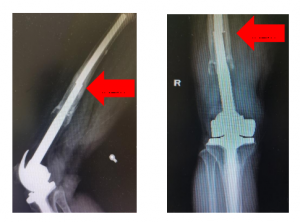

技术硬实力!济宁市第一人民医院成功开展高难度肿瘤膝关节假体翻修术

近日,济宁市第一人民医院骨关节外科成功为一名肿瘤假体人工膝关...